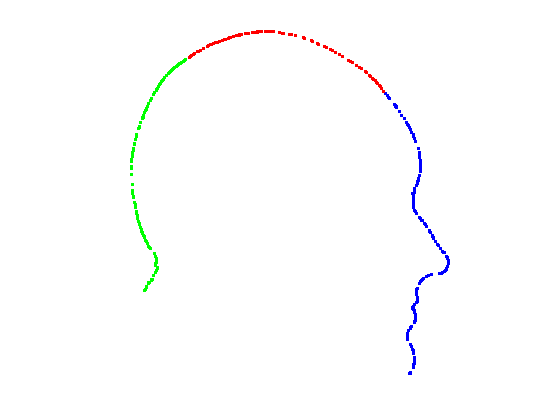

In order to find the facial contour we implemented a piecewise ICP process across the glocal symmetry plane. Each head is first rotated such that its global symmetry plane is coincident with the Y-Z plane. The facial region, as defined by the sparse model fit is then divided into a set of horizontal strips (we use 20mm steps between the nasion and pognion) in the dimension, with the back of the head being cropped out. We apply our trimmed ICP algorithm to each separate strip, so that a local symmetry plane is found for each strip and the facial contour is found by intersecting this sequence of local symmetry planes with its corresponding facial strip. For each strip (index ), we use the strip below and the strip above in the trimmed ICP process in order to reduce the sensitivity of the local symmetry planes to noise. This process is only applied to the face and the cranial region is dealt with as a whole. This is because, in strips, it does not provide sufficient constraints for ICP to lock onto and the two surfaces can slide over each other freely. Fig. 12 shows facial local symmetry contours deviating from the global symmetry plane. Points on the head profile are then extracted by detecting mesh arcs that cross a symmetry plane and linearly interpolating to extract 3D vertices that lie on that symmetry plane.

|

|

|

|